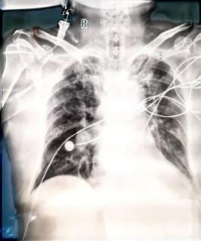

2025/12/01床旁胸片

2025/12/01床旁胸片:1.左侧胸腔积液2.双肺感染,治疗后复查

2025/12/08床旁胸片提示双肺感染好转。血液净化支持下氧合指数逐渐改善,予以血液净化下机。